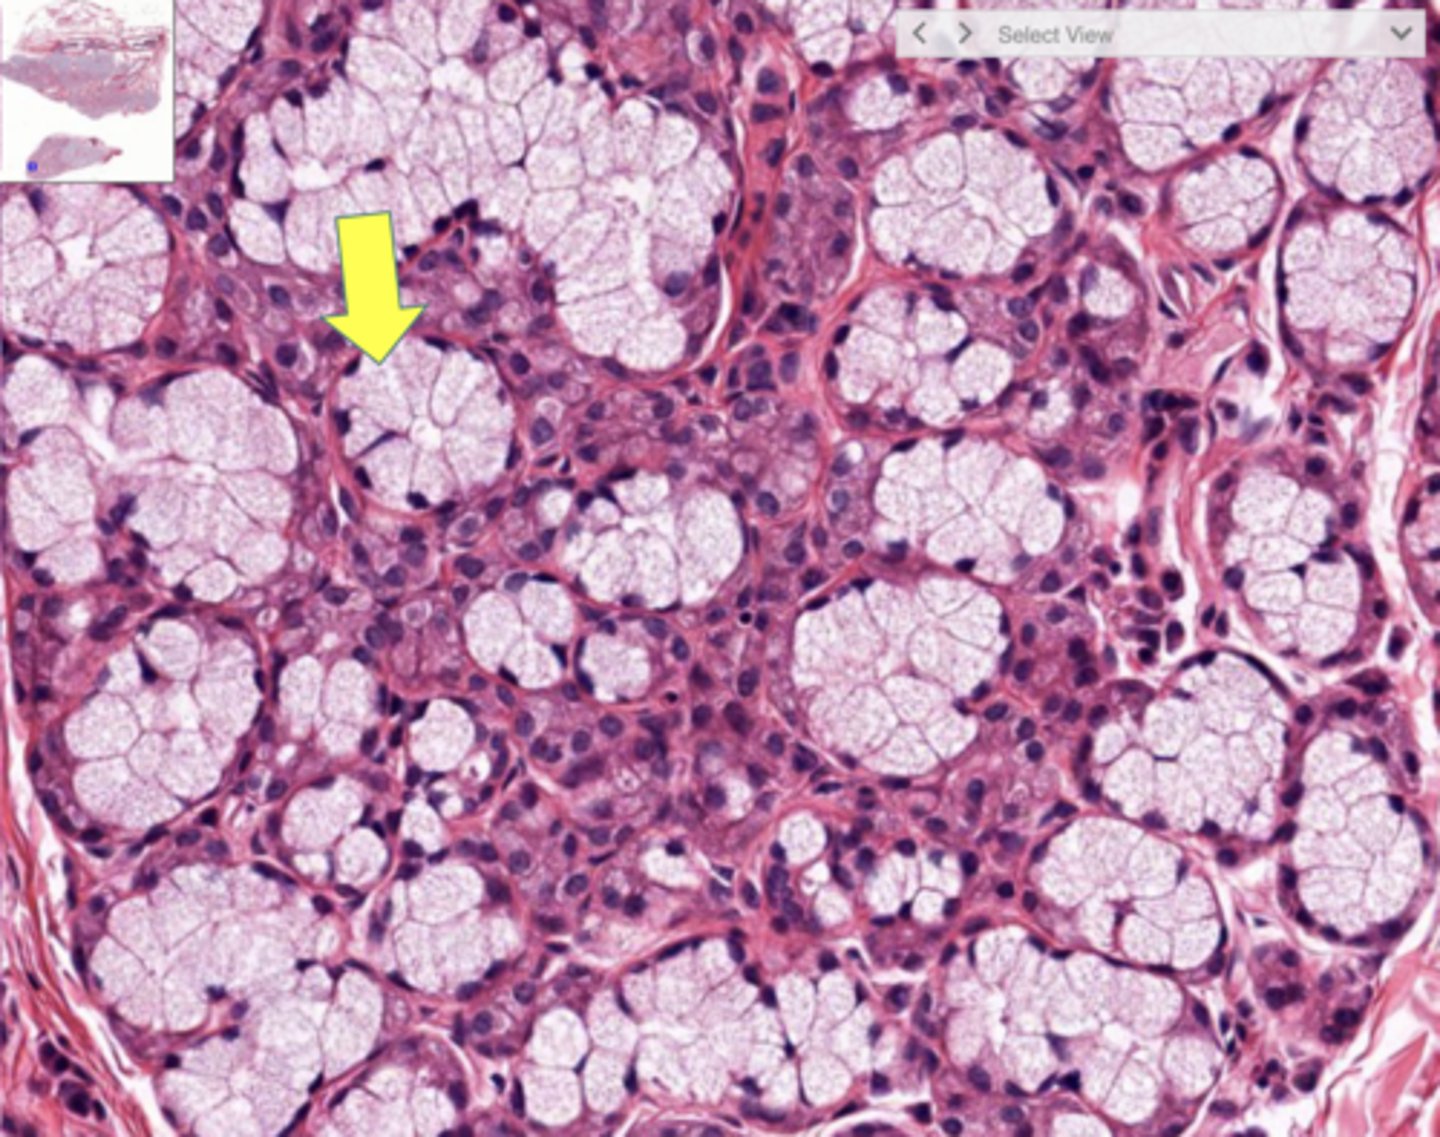

Pancreas

Acinar cells

Blue circle

Pancreatic islet

Pancreatic islets

What structure contains the endocrine portion of the pancreas?

Blood sugar levels

What homeostatic variable is regulated by the endocrine portion of the pancreas?